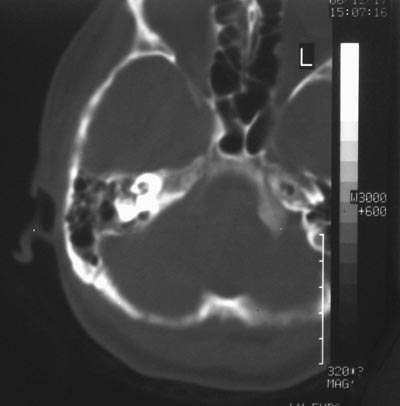

女,29岁,外伤15小时,自诉右侧耳朵流血,听力下降。

乳突内积血吗?店家吝啬哦

枕骨像是有骨折哦!

颅底骨折,儿漏,建议高分辨ct.

颅底骨折..

乳突小房积血,建议行颅底hrct.

颅底骨折.

乳突小房好象看到液平了,建议估算法重建薄层看看哪里有骨折

首先祝贺发帖成功,另乳突内似见低密度影考虑外伤致。